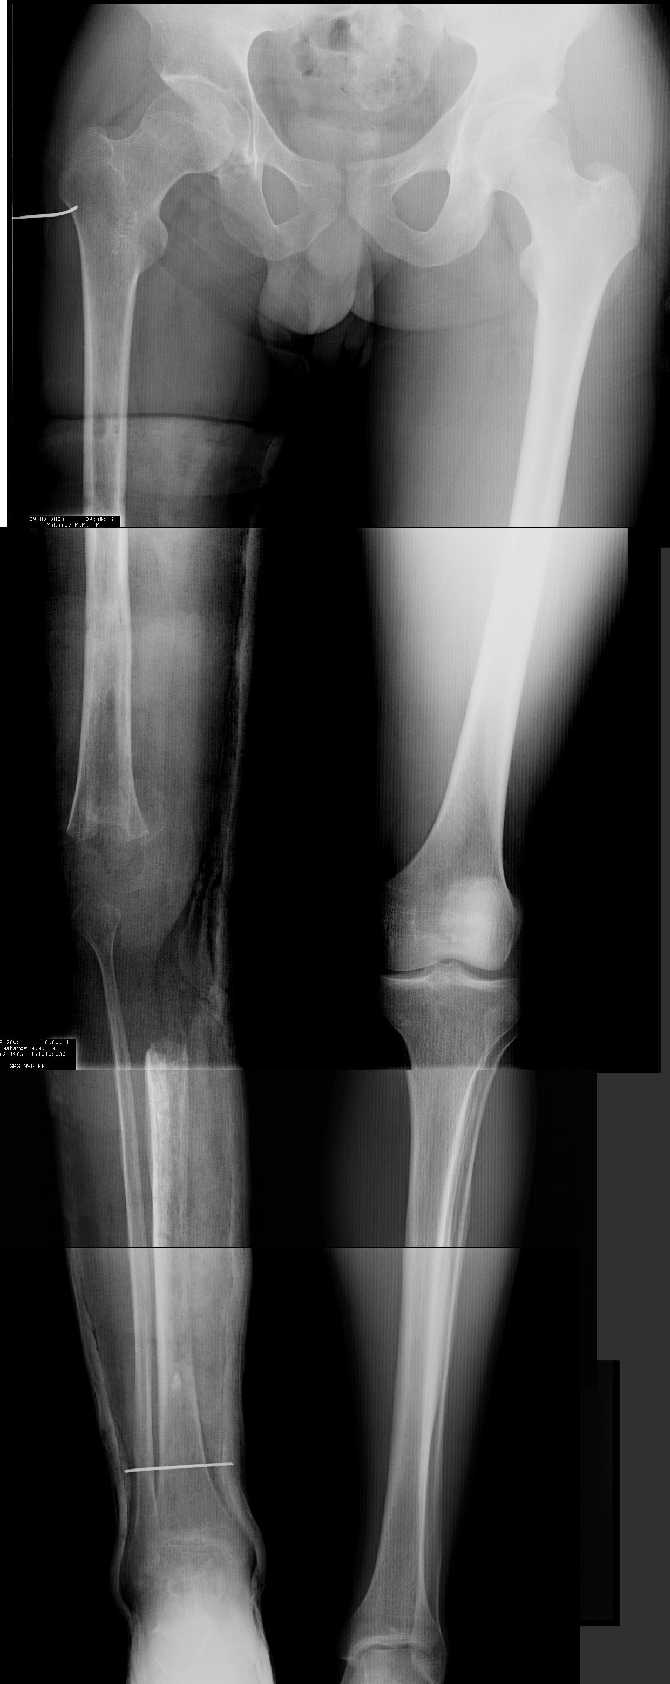

Прежде всего необходимо выполнить рентгенографию в таком положении, как это показано на рис.

После этого представится возможность оценить ось и сравнитьеё с нормой Рисунки из кники Dror Paley - Принципы коррекции деформаций. Этой теме посвящены 800 страниц. Хотя, учитывая контрактуру, это исследование не будет исчерпывающим.

1. Иллюстрации - во вложении.

Два бедра после эндопротезирования.

Авторы операции долго думали почему больная хромает.

Сдклали снимок - одна нога короче почти на 3 см.

Здоровый человек и то будет хромать.

2. Другой пример - дефект после инфицирования коленного эндопротеза.

Предполагалось, что величина дефекта 11-12 см. Так получается, если

сделать снимок только области коленных суставов. Определить

укорочение сложно, так как нога просто болтатется.

Сделали снимок "от и до" - величина дефекта 17 см.

Правда эта иллюстарция сделана на цифровом рентгеновском аппарате.

Больной стоит, а трубка передвигается сверху вних, последовательно

выполняя рентгенограммы. В данном случае - 4 штуки.